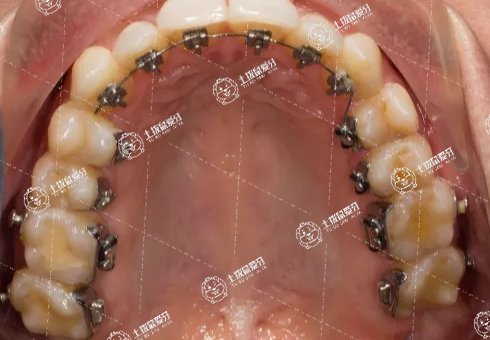

牙齒擁擠矯正通常需要一年或者兩年的時(shí)間。每個(gè)人牙齒的情況都不太一樣,所以牙齒矯正需要的時(shí)間也不一樣,具體時(shí)間還需要到專業(yè)牙科就診檢查之后才能確定。牙齒矯正的材料和方式有很多,例如功能托槽、活動(dòng)托槽、固定托槽等,可以根據(jù)自己的實(shí)際情況來(lái)選擇合適的材料和治療方案。在進(jìn)行牙齒矯正時(shí),不要吃太甜的食物,避免齲齒的出現(xiàn)。

牙齒矯正經(jīng)歷的步驟大致為拍片、制定矯牙方案、戴牙套、牙齒排齊、收牙縫、調(diào)咬合、精調(diào)、摘牙套、戴保持器等,根據(jù)每個(gè)人牙齒情況不一樣,所需時(shí)間不一樣。